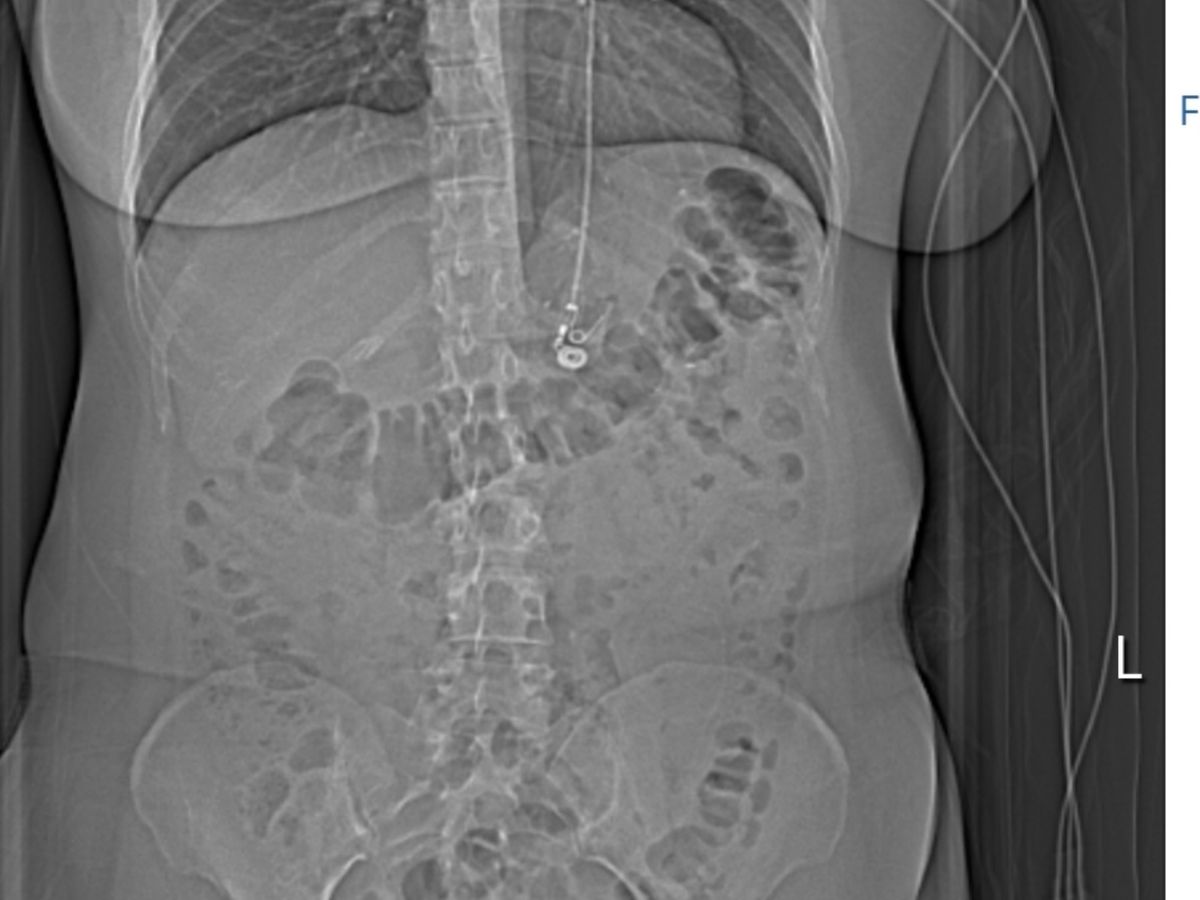

My name is Erin Powell, and I’m reaching out during one of the most challenging times in my life. In October 2018, I underwent gastric bypass surgery, hoping for a healthier future. Instead, it has been a nightmare of repeated complications, surgeries, and hospital stays.

Just two weeks after the initial procedure, I was rushed back to the hospital with a bowel obstruction. Over the years, my journey has included multiple surgeries for a kink in the jejunostomy, gallbladder removal, and even a reversal of the bypass itself earlier this year. Each procedure brought new complications, including sepsis, ICU stays, and blood clots that have left me on blood thinners for months.